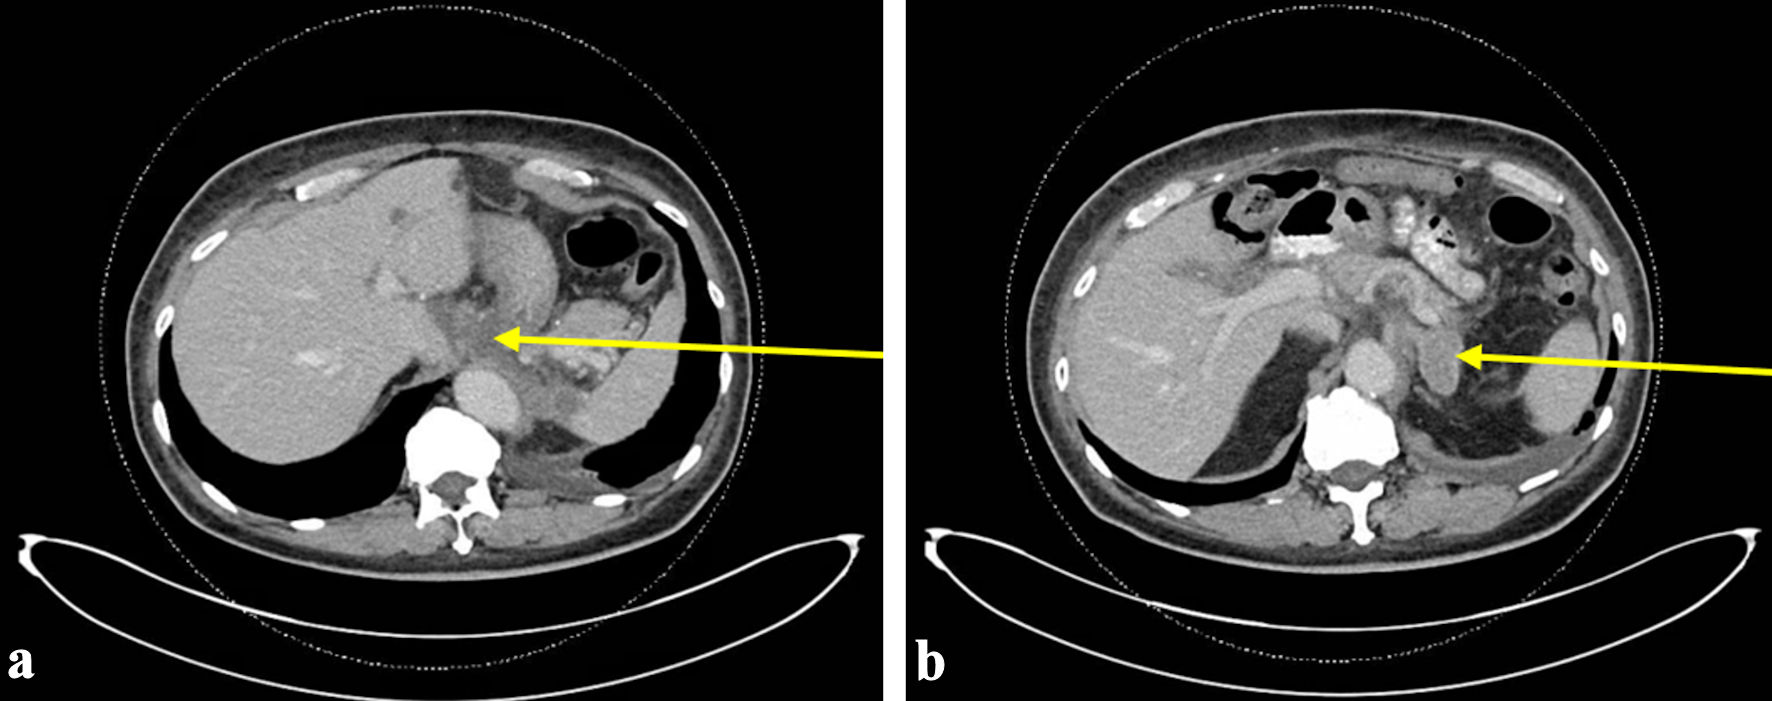

This case is a 69-year-old man with a history of hypertension, hyperlipidemia, hypothyroidism, and metastatic malignant GIST who presented to the emergency department (ED) with gingival bleeding. He was originally diagnosed with GIST 9 years prior to development of DIC, for which his treatment included gastric wedge resection of the primary tumor and 12 months of adjuvant imatinib. Three years prior to developing DIC, he was found to have metastatic recurrence involving the liver and the region adjacent to the gastroesophageal junction. Endoscopic fine needle aspiration was performed on celiac lymph node, which demonstrated GIST, including 11 mitoses per 10 high power field, and Ki-67 of 14%. Next generation sequencing was positive for KIT exon 11 mutation with deletion of Trp557_Lys558 and negative for any PDGFRA mutations. Based on his genotypic information, he was initiated on imatinib 400 mg daily. His case was reviewed by a multidisciplinary tumor board that recommended against surgical intervention for residual disease burden. Shortly prior to developing DIC, a follow-up computed tomography (CT) scan demonstrated progression of disease with worsening pulmonary nodules, bilateral retroperitoneal adenopathy, soft tissue thickening around esophageal hiatus, and new left adrenal lesion (Fig. 1). Biopsy of adrenal lesion confirmed metastatic GIST. He remained on imatinib 400 mg daily at time of presentation.

Figure 1. The most recent CT abdomen and pelvis performed prior to initial ED visit with bleeding. CT scan at this time demonstrated progression of disease with worsening pulmonary nodules, bilateral retroperitoneal adenopathy, soft tissue thickening around esophageal hiatus (arrow) (a), and new left adrenal lesion (arrow) (b). ED: emergency department; CT: computed tomography.